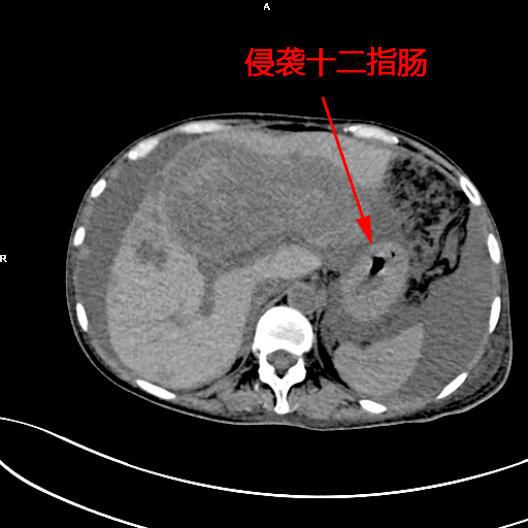

患者陳女士,57歲,汕頭潮南人,2個月前出現右上腹痛,在汕頭大型三甲醫院确診爲膽囊癌,因腫瘤爲晚期,已擴散至肝髒、十二指腸,患者放棄在汕頭治療,回家後自行采用中藥治療。近期右上腹痛加重,反複排黑便,遂來我院住院,診斷爲膽囊癌伴活動性出血。

5月11日下午,内三科主任李旭丹、影像科副主任胡志華上台施術。通過粵東領先的飛利浦DSA造影顯示,患者腫瘤供血血管豐富,膽囊動脈造影可見腫瘤染色明顯,有造影劑外溢,提示部分血管末梢有破裂出血現象,探查胃十二指腸動脈及腸系膜上動脈未見出血征像,豐富的血供使腫瘤能獲取大量的營養快速生長,血管末梢的破裂出血導緻患者反複黑便。